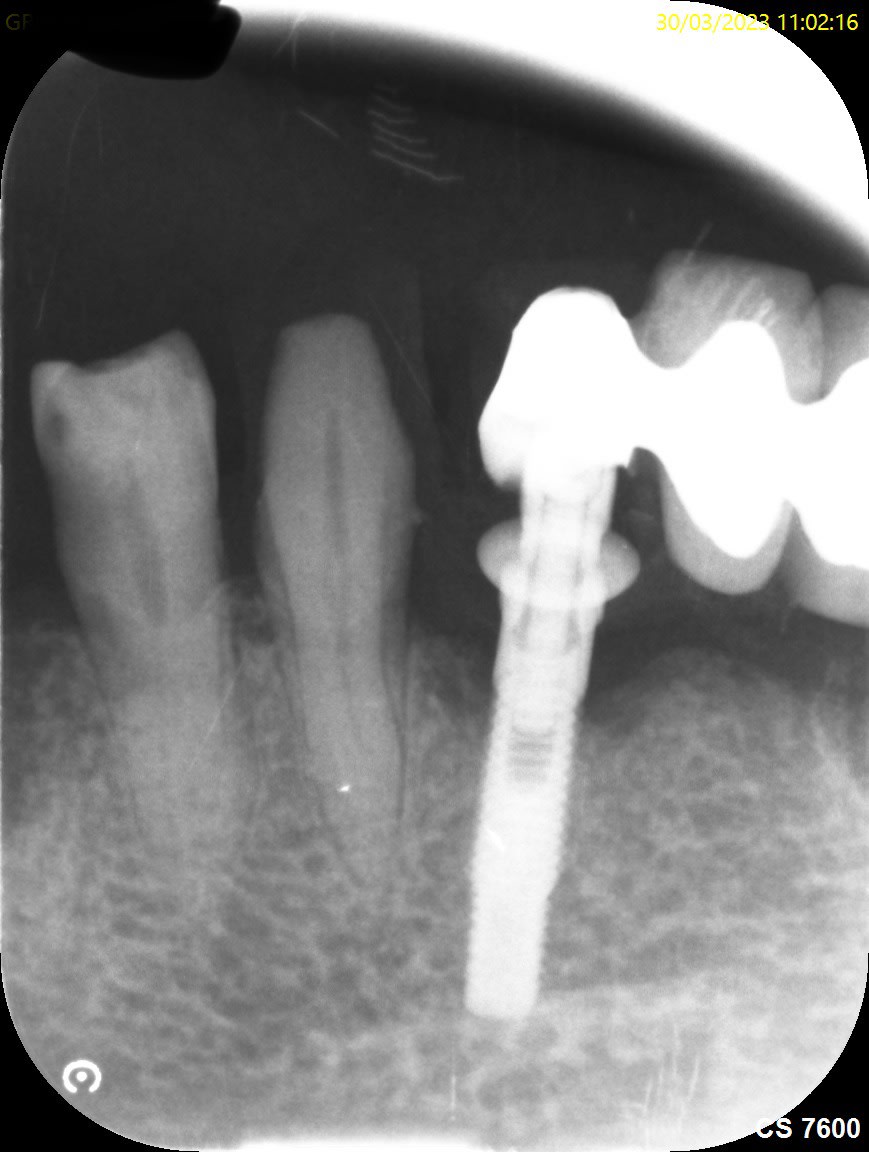

Voici la rétro